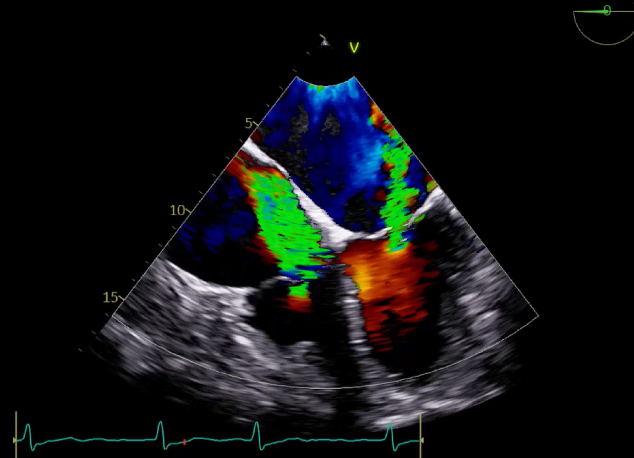

TEE LVOT切面返流量评估

TEE 4-Ch view返流量评估

3D-color:残余少量返流